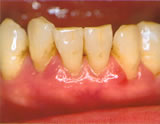

- 中度の歯周炎

歯茎が下がり、赤黒くぶよぶよと

変化しています。